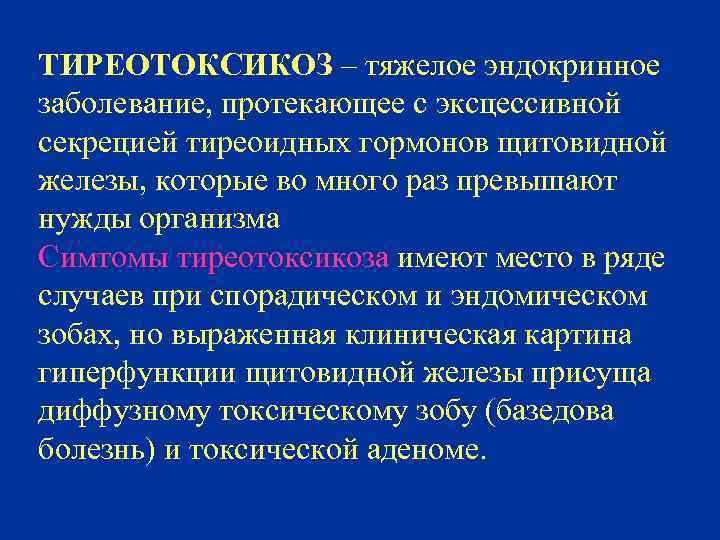

ТИРЕОТОКСИКОЗ – тяжелое эндокринное заболевание, протекающее с эксцессивной секрецией тиреоидных гормонов щитовидной железы, которые во много раз превышают нужды организма Симтомы тиреотоксикоза имеют место в ряде случаев при спорадическом и эндомическом зобах, но выраженная клиническая картина гиперфункции щитовидной железы присуща диффузному токсическому зобу (базедова болезнь) и токсической аденоме.

ТИРЕОТОКСИКОЗ – тяжелое эндокринное заболевание, протекающее с эксцессивной секрецией тиреоидных гормонов щитовидной железы, которые во много раз превышают нужды организма Симтомы тиреотоксикоза имеют место в ряде случаев при спорадическом и эндомическом зобах, но выраженная клиническая картина гиперфункции щитовидной железы присуща диффузному токсическому зобу (базедова болезнь) и токсической аденоме.